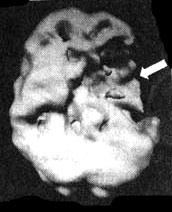

ПК связана многими связями с лимбической системой. Она посылает запрещающие сигналы, которые помогают ей держать лимбическую систему под контролем Она дает возможность «думать головой, а не только эмоциями». Когда в этой области мозга, особенно в ее левой части, отмечается снижение активности или повреждение, ПК уже не в состоянии должным образом влиять на лимбическую систему, а это может вызвать повышенную предрасположенность к депрессии — в том случае, если лимбическая система начинает работать слишком активно. Классической иллюстрацией тому могут стать пациенты, перенесшие кровоизлияние в левую лобную долю мозга. У шестидесяти процентов таких больных в течение первого года после инсульта развивается тяжелая депрессия.

Инсульт в левой фронтальной доле

Трехмерное изображение поверхности, вид сбоку.

Трехмерное изображение, нижняя поверхность.

Обратите внимание на обширную «дыру» активности мозга, расположенную в левой фронтальной доле.